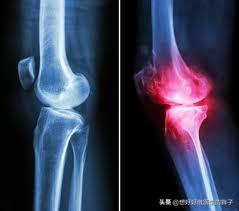

第一,当骨刺形成的过大,或者是形成的范围过广,就会影响到患者关节活动的屈伸范围,并导致疼痛。尤其是在一些比较大的关节,比如膝关节。在临床上因为膝关节骨质增生,进行手术或者保守治疗的患者是往往是最多的。